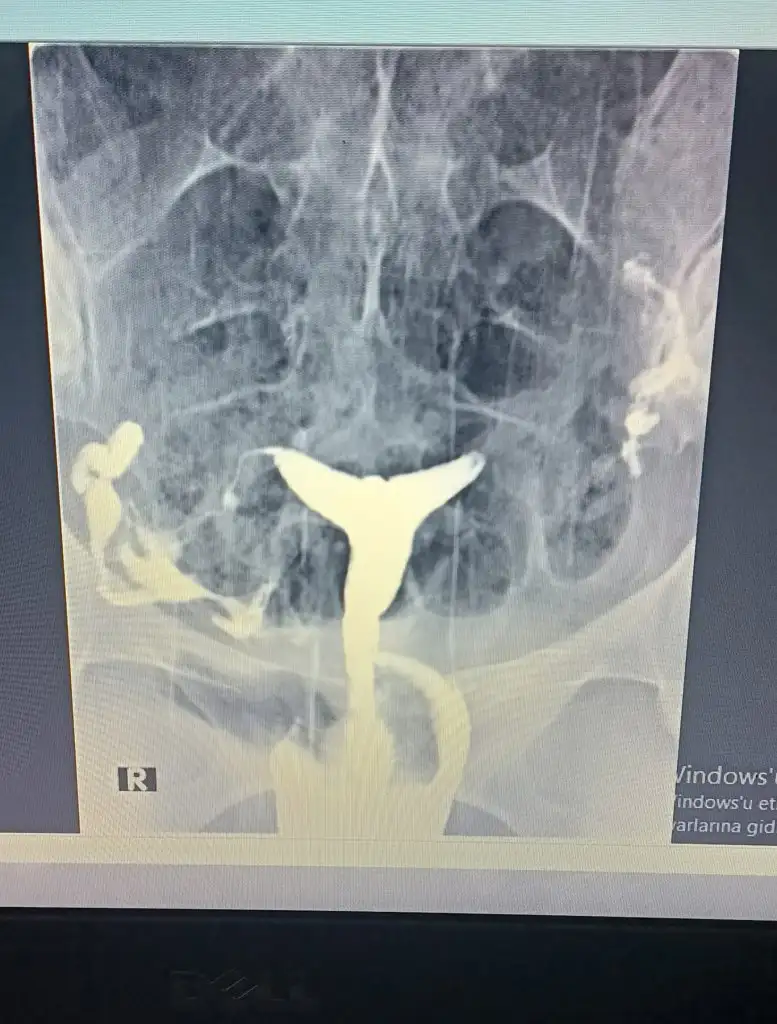

Aynen dedin sen bana..bu hsg cevabımı?Niqu Bir de gerçekten sanki sağda genişleme var. Şansıma hep sağdan yumurtlama oluyordu hiç tutmadı belki de sebep bu şişme. Tüpün icinde sıvı varsa tüp bebek yapsan bile tutmuyormus. Bilgisi olan varsa yorum yapabilir

Canim ben çok okudum hidrosalpenks bunun adı. Tüp bebek bile yapılmıyor eğer bu sıkıntı varsa. Tüpten rahme sıvı akıyormuş bu da embriyonun oluşmasını engelliyor. Tabi eğer gerçekten tüpte sıvı varsa benimGebe kalamamak bununla alakası yok..demek zamanı gelmemiş kuzum.İn şa Allah boşa ameliyata girmemiş olursun..seni çok merak ediyorum..nedense bu doktorlara inamım hiç kalmamış..Sonuç güzel olsun

Tamam o zaman hayırlısi neyse o olsun kuzum senin için..eğer sebeb buysa kurtul hemenCanim ben çok okudum hidrosalpenks bunun adı. Tüp bebek bile yapılmıyor eğer bu sıkıntı varsa. Tüpten rahme sıvı akıyormuş bu da embriyonun oluşmasını engelliyor. Tabi eğer gerçekten tüpte sıvı varsa benim

Doktor yorumunu yok mu rapordaNiqu Bir de gerçekten sanki sağda genişleme var. Şansıma hep sağdan yumurtlama oluyordu hiç tutmadı belki de sebep bu şişme. Tüpün icinde sıvı varsa tüp bebek yapsan bile tutmuyormus. Bilgisi olan varsa yorum yapabilir